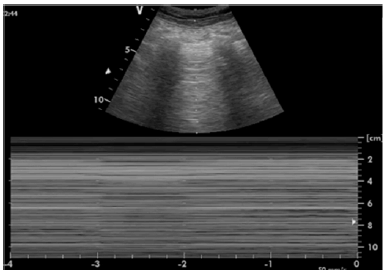

Um paciente em pós-operatório imediato de nefrectomia total esquerda evolui com franca taquidispneia, taquicardia e hipotensão. Ao realizar exame point of care exibido abaixo, prontamente o médico anestesiologista levanta sua hipótese diagnóstica.

Assinale a alternativa que apresenta o diagnóstico e o provável fator desencadeante desse quadro.